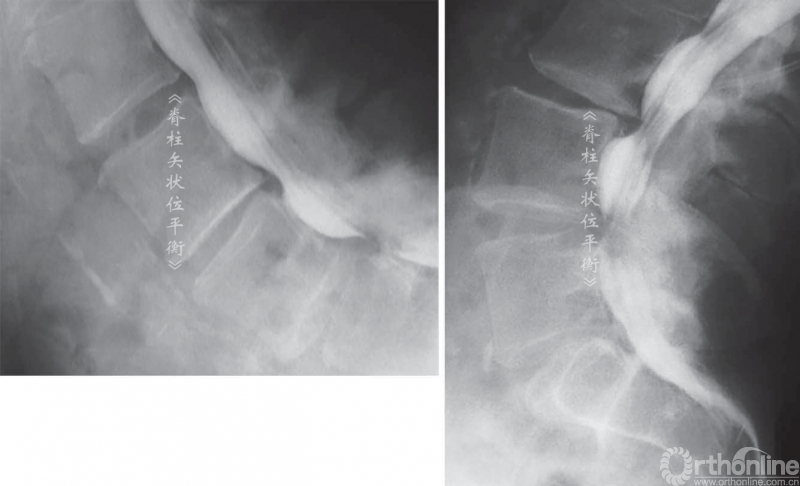

人类的衰老退变是不可避免的,而且可能受到遗传因素和机械因素的影响(脊柱限制性的专业运动或重复性的体育运动而加速。椎间盘在18岁的时候开始脱水变性,这可以引起生理性腰椎前凸减小图1L5S1减小25°, L4L5减小15°,上腰椎减小1°2°。

图1 随着老龄化,下腰椎椎间盘扁平,关节突及棘突增宽,导致腰前凸角度减小

实际上腰椎发生退变的顺序是从下往上的进行的,这是由于下腰椎L5S1甚至L4L5相对于骨盆的铰接位置决定的2。退变导致L4S1的脊柱前凸角度明显减小,该区域占据腰椎前凸角度的2/3